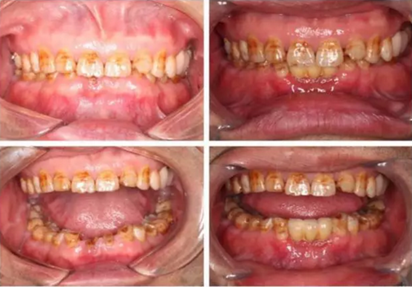

患者,男性,47歲,全身情況良好,無手術禁忌,口內(nèi)因下前牙缺損松動不美觀來院。初診檢查時發(fā)現(xiàn)患者前牙深覆合,下頜32、42缺失。31、41松動二度,切緣磨耗嚴重,可探及髓腔,無保留價值。X-RAY檢查顯示:下頜前牙區(qū)寬度狹窄,咬合空間不足,無法行常規(guī)種植修復.

下圖是術前資料